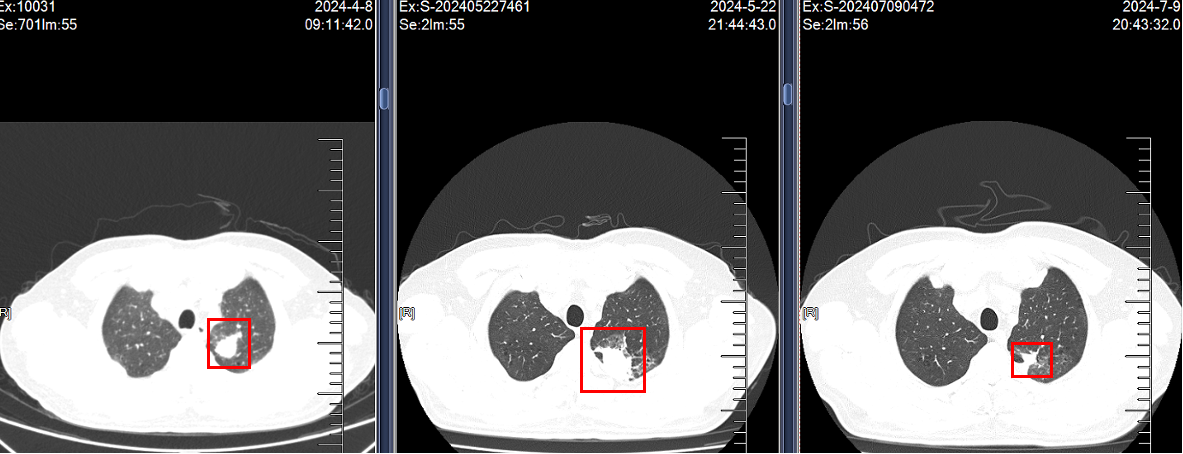

2.2024.5.22复查:咯血增多,胸部CT示病灶明显增大,评估疾病PD,停用特泊替尼。

3. 2024.5.27:予培美曲塞+卡铂化疗,出现皮疹(口服氯雷他定片后4-5天消退)。

4. 2024.6.17至今:行培美曲塞二钠0.8g + 卡铂400mg + 舒格利单抗1200mg(共20程,维持治疗中,无不良反应)。

临床随访影像对比